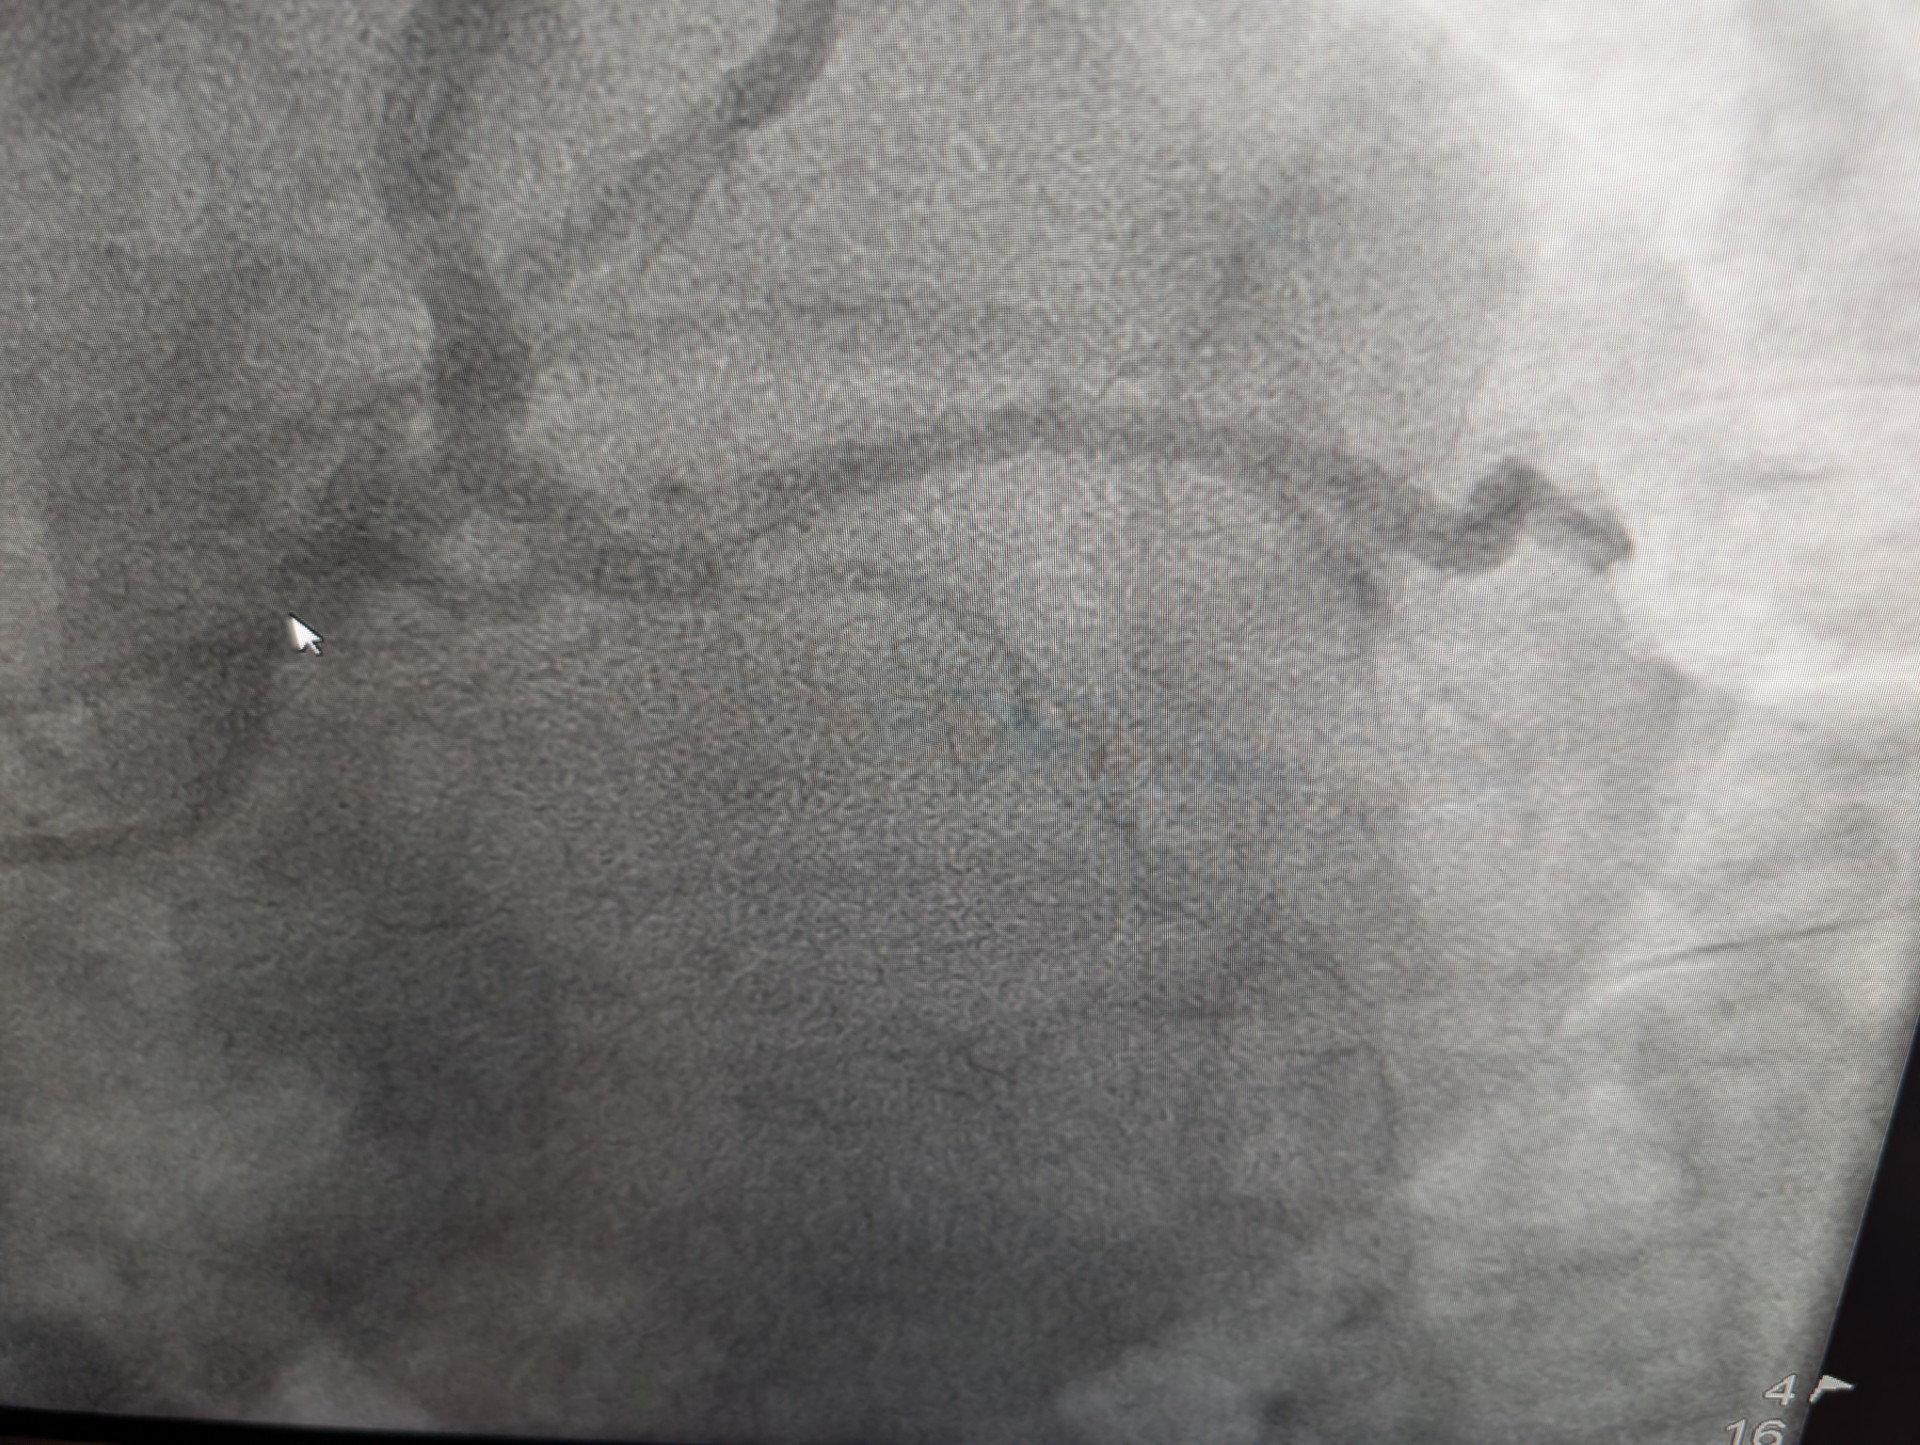

Before: